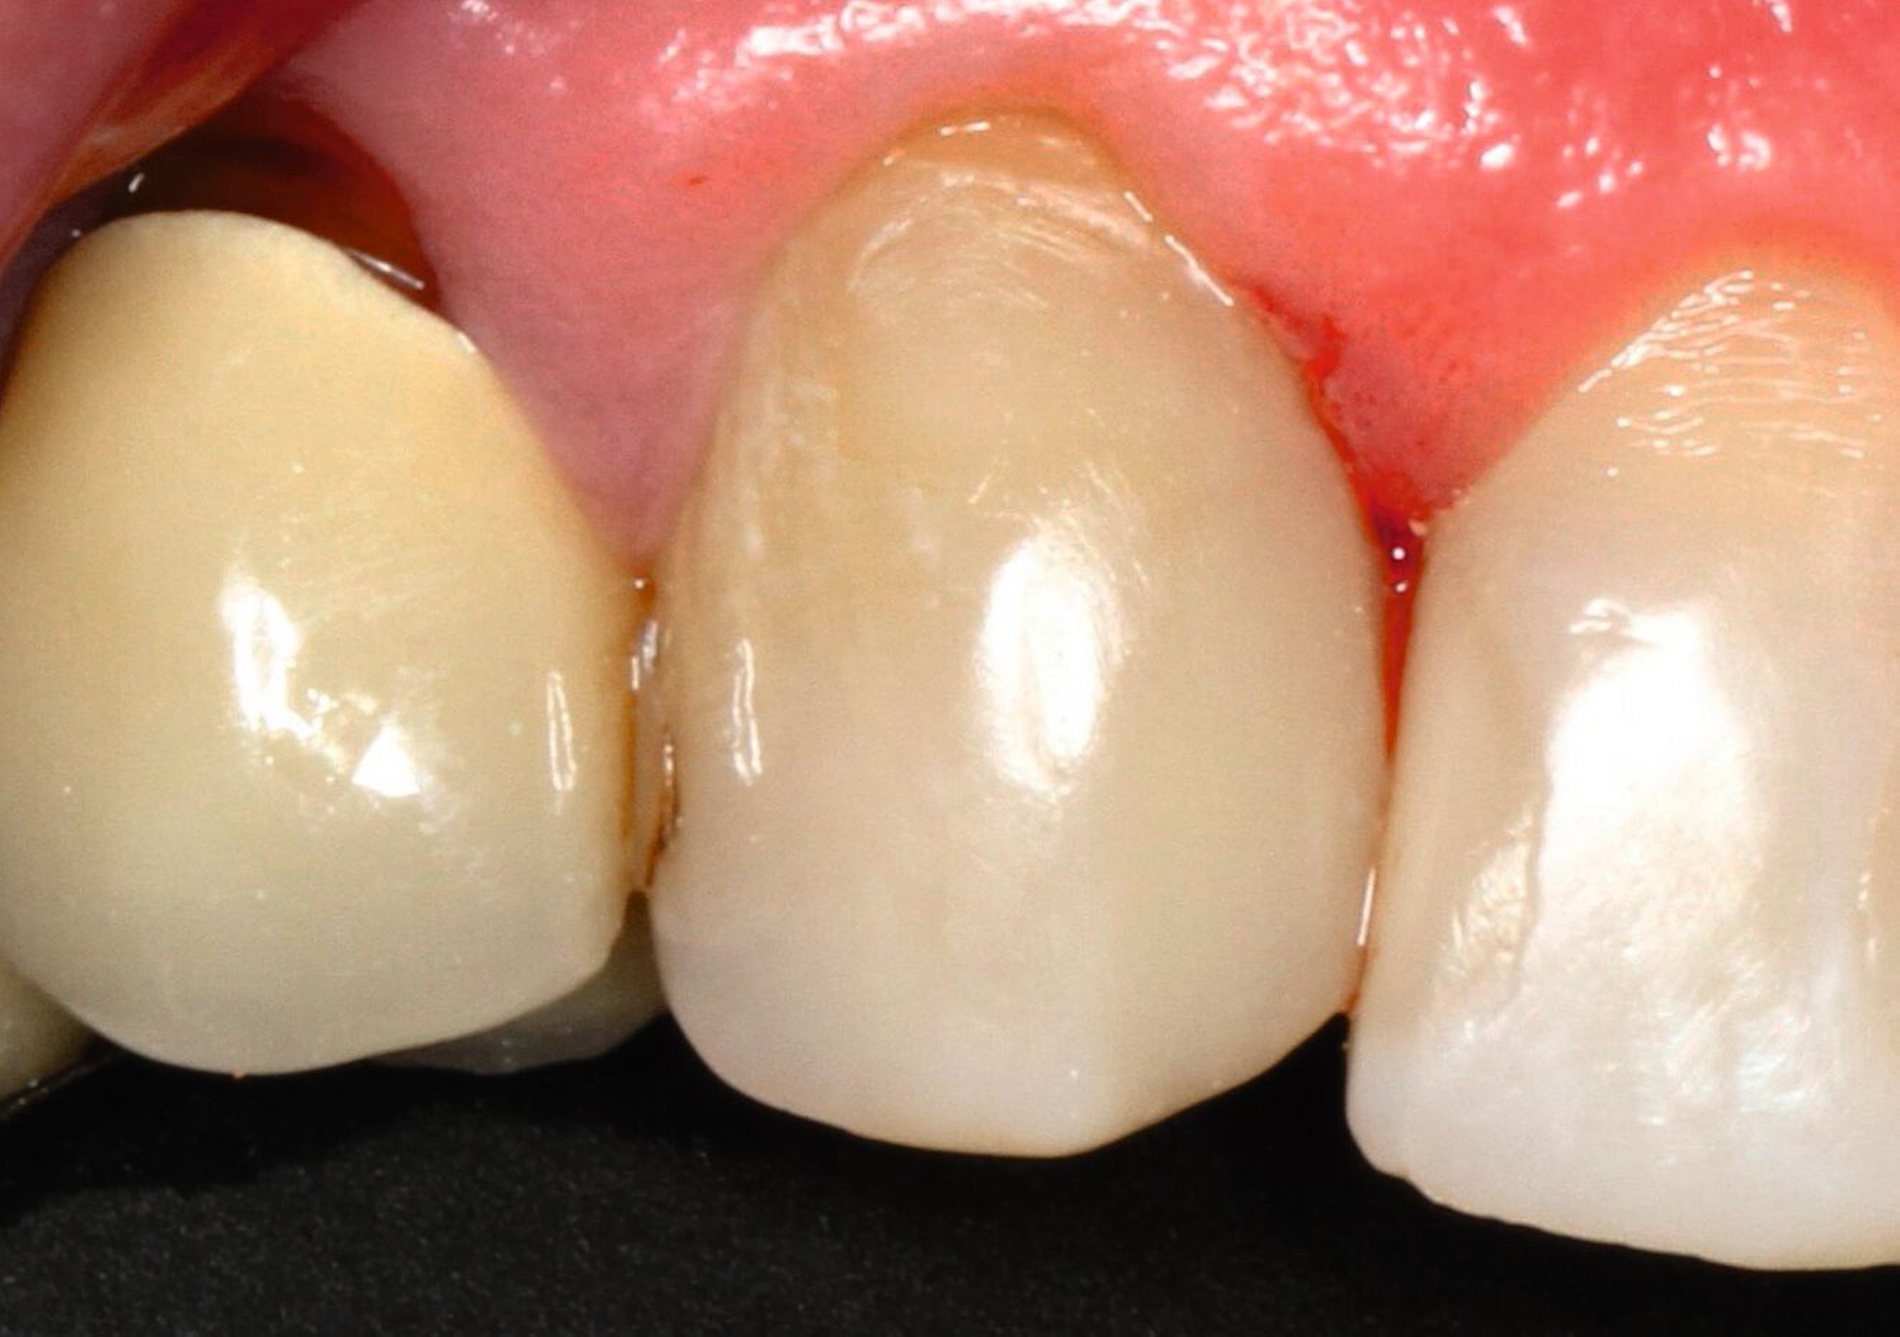

Die dentale Ausgangssituation zeigte im Seitenzahnbereich ein suffizient konservierend und prothetisch versorgtes Gebiss der zweiten Dentition sowie im Frontzahnbereich nicht kariogene Zahnhartsubstanzverluste und eine defekte Krone mit Sekundärkaries (Abbildungen 1 und 2).

Zur Verbesserung der Ästhetik und des Wohlbefindens des Patienten standen die Harmonisierung der Lachlinie und des Frontzahnbogens sowie Farb- und Formkorrekturen der Oberkieferfrontzähne im Fokus. An den Zähnen 11 und 21 waren Zahnhartsubstanzverluste durch Erosion und Attrition zu erkennen. Zahn 23 hatte ebenfalls einen erosiven Defekt, Zahn 13 eine farblich abweichende Kompositrestauration und die Zähne 14 und 24 wiesen keilförmige Defekte zervikal der Kronenränder auf, die einen suffizienten Randschluss haben (Abbildung 1a).

Die Zähne 11, 21 und 32–42 wiesen aufgrund des Zahnverschleißes stark verkürzte klinische Kronen auf. Durch diese Zahnhartsubstanzverluste sind die genannten Zähne über die Zeit elongiert – gut erkennbar an dem in Richtung Okklusionsebene verschobenen Verlauf des Gingivalsaums –, wodurch sich ein frontaler Tiefbiss und in Protrusion eine verzahnte Frontzahnführung im Schlüssel-Schloss-Prinzip mit veränderter Rot-Weiß-Ästhetik adaptiert haben. Daraus resultiert ein verringertes Platzangebot in statischer und in dynamischer Okklusion (Abbildungen 1b und 1d).